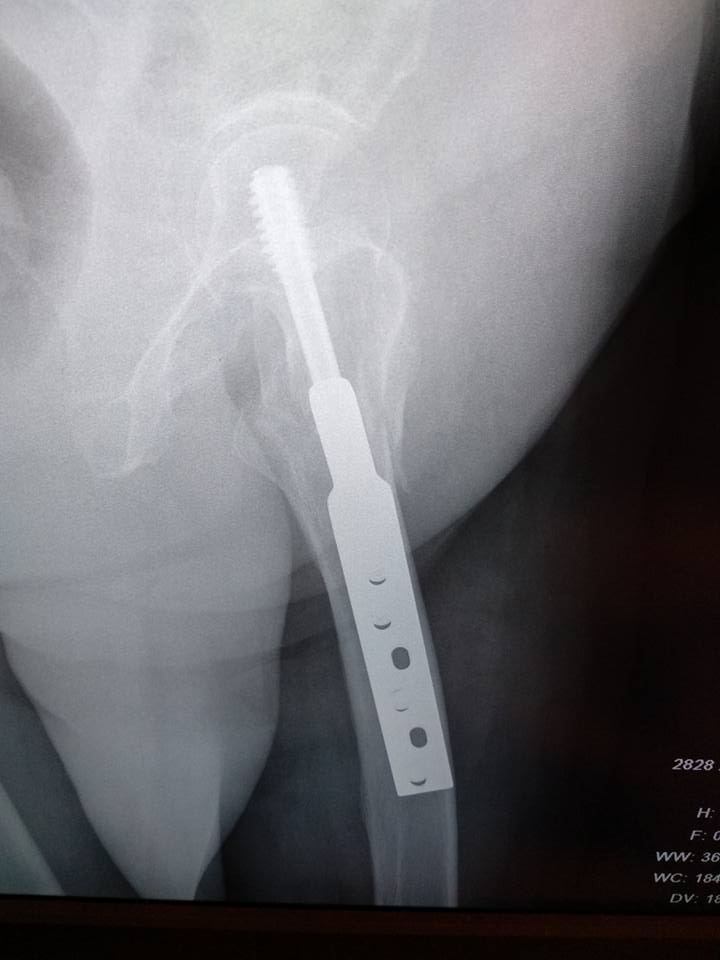

Re: Межвертельный перелом после фиксации DHS

Gamma long/PFN long! Неправильный выбор фиксатора, и имеем то, что имеем!

Полностью согласен с коллегой перелом типа А3 показания к проксимальному стержню

Смена метода напрашивается!!! DHS удалить и поставить PFN-a

Да, при телескопировании медиализация дистального отломка еще увеличится. Надо пересинтезировать. Подойдет любой PFN, необязательно длинный.

Коллеги, спасибо за советы! Думаем в том же направлении. Сомнения были относительно того, есть ли у перелома хоть небольшой шанс срастись при таком стоянии отломков.

Виталий, дорогой! Допустим, небольшой есть. И что? Ведь не в рулетку играем! Надо сделать остеосинтез, обеспечивающий максимальные шансы на успех, а не рассчитывать на "авось".

Боимся инфекции!

Если там сейчас все чисто, риск инфекции немногим выше, чем при первичном остеосинтезе. А более стабильная фиксация - тоже мера профилактики инфекции.

Это называется медиализация, известный процесс для DHS. Специально для этого создан механизм скольжения гвоздя внутри пластины. Раньше у нас такое часто случалось, когда делали DHS при реверсных переломах. В таких случаях лучше изначально ставить Гамма.